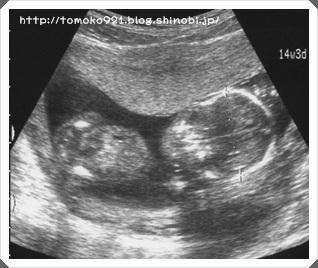

どれどれ、赤ちゃんは元気に育ってるかな?

おぉ♪ 大きくなってる(ノ´∀`*)♪

身長は、約10cm。1ヶ月前の2.5倍!

すくすくと育っております(ノ´∀`*)